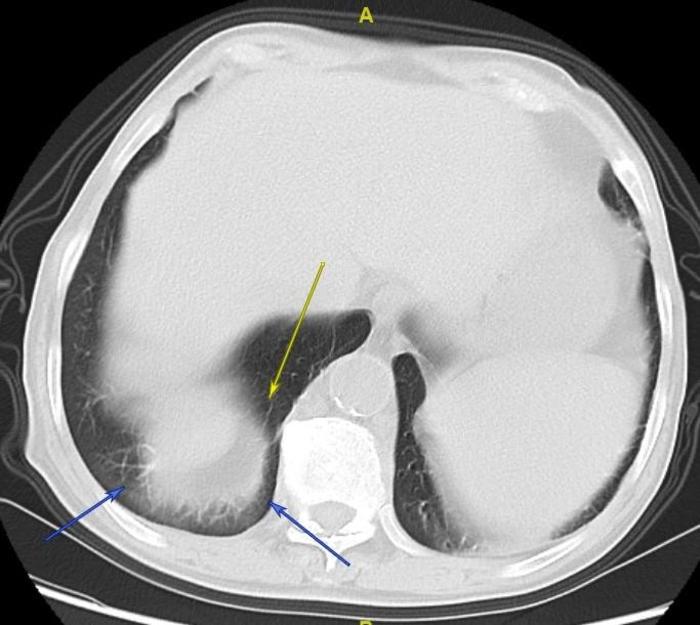

一个病人,门诊来就诊时,当地医院以为有一个较大的肺癌,认为要肺穿刺检查。如下图。箭头指示处好像是一个肺癌。

我一看,认为是肝脏的伪影,认为没有肺肿瘤。进行了薄层CT。果然,如下图,箭头指示处是肝脏形成的伪影,肝脏向右后方突起,局部狭窄。